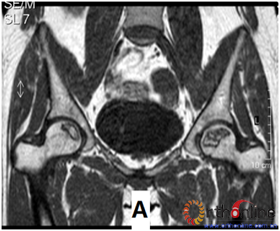

在股骨头坏死塌陷与外侧柱存留及存留宽度的关系深入研究的基础上,我们提出了以股骨头三柱结构为基础的股骨头坏死分型(中日友好医院分型(16)),此分型以三柱结构为解剖基础,根据MRI(ARCOⅠ~Ⅱ期)或CT(ARCOⅡ~Ⅲ期)冠状位正中层面影像改变(坏死灶占据三柱情况),分为A、B、C三大型,C型又分为C1、C2、C3三型,分别代表外侧柱存留情况(图4)。用此型对大量股骨头坏死患者进行自然进展或保头手术效果的研究,发现此分型应用的方便性,准确性均优于日本骨坏死调查班(JIC)提出的股骨头坏死分型(A、B、C1、C2四型)(5)。但仅限于本中心病例,期望同行用此分型法分析各自的病例,以获多中心研究的数据。

图4 依据三柱理论的CJFH 股骨头坏死分型示意图及MRI 影像。A 型:坏死灶占据内侧柱,B 型:坏死灶占据中央柱和内侧柱,C1 型:坏死灶占据三柱,但外侧柱有部分存留,C2 型:坏死灶占据外侧柱及部分中央柱,C3 型:坏死带穿透整个股骨头三柱皮质及骨髓

Fig.4 Schematic diagram and MRI of China-Japan Friendship Hospital (CJFH) classification for osteonecrosis of the femoral head based on three pillars. Type A: the necrosis involved the medial pillar. Type B: the necrosis involved both medial and central pillars. Type C1: the necrosis involved the three pillars but the partial lateral pillar preserved. Type C2: the necrosis occupied all lateral pillar and partial central pillar. Type C3: the necrosis involved the three pillars including the cortical bone and marrow.